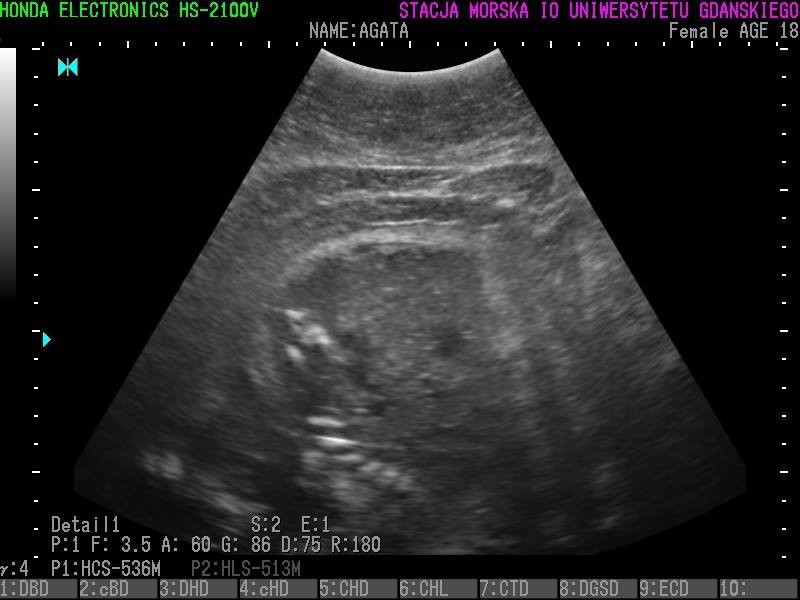

Wszystkie helskie foki - czyli Agata, Ewa, Unda Marina i Ania - są w ciąży. To wyniki badań ultrasonograficznych, które przeprowadzono w miniony piątek (23 grudnia).

• Z radością więc informujemy, że tego roku wszystkie nasze cztery samice spodziewają się potomstwa - czytamy na profilu Fokarium.